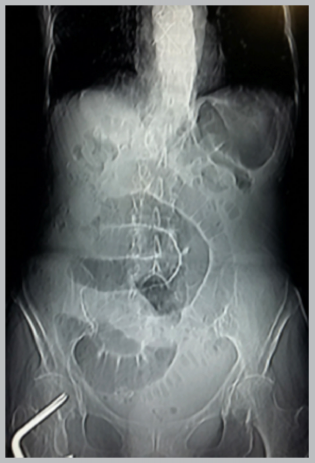

Figure 1 Abdominal X-ray. Pneumatization and dilation of small bowel loops with characteristic arrangement of obstructive abdomen. Absence of gas in the rectal vault.

Laboratory tests showed 7590 leukocytes/mm3 with 89.1% neutrophils. On admission, an abdominal X-ray (figure 1) demonstrated pneumatization and dilated small bowel loops characteristic of abdominal obstruction. The CT scan also showed dilated bowel loops and air-fluid levels (figure 2-A and 2-B). The patient subsequently was admitted with the diagnosis of bowel obstruction. Nine hours after admission she developed leucopenia 860/mm3 with 45.3% neutrophils and a C-reactive protein (CRP) of 190.80 mg/L. Thirty-three hours after admission, the clinical picture worsened, with greater abdominal distention accompanied by 1460/mm3 leukocytes, 55.5% neutrophils, a CRP of 216.7 mg/L, and a procalcitonin (PCT) of 4.42 ng/mL.